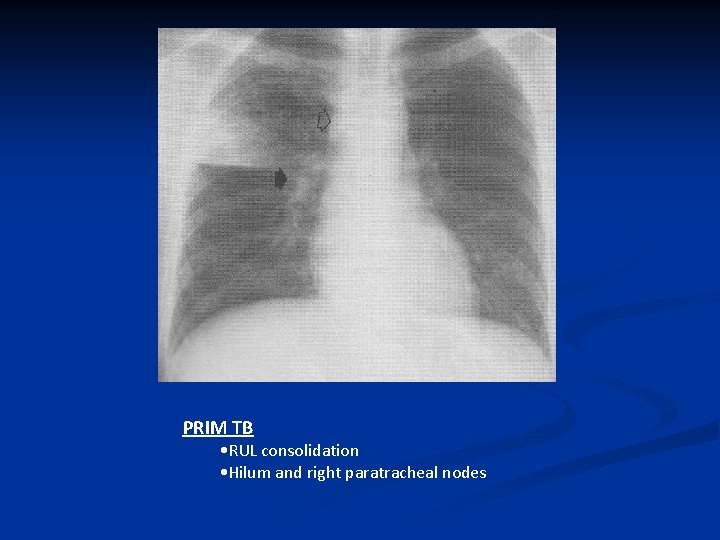

PRIM TB • RUL consolidation • Hilum and right paratracheal nodes